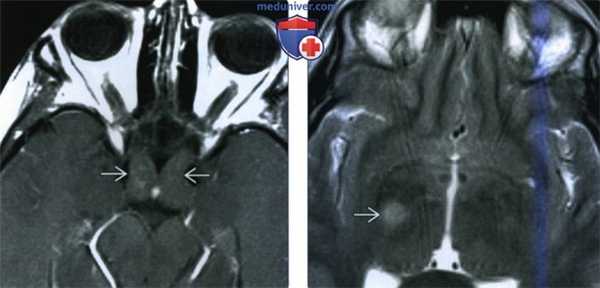

Рост и регресс мультифокальной опухоли: (А) При МРТ у пятилетнего мальчика с нистагмом и кивательными движениями головы выявлено увеличение хиазмы, более выраженное слева.

(Б) Изменения хиазмы сопровождаются двусторонним утолщением зрительного нерва, более выраженным слева.

Хорошо заметное низкоинтенсивное кольцо, более широкое слева, окружает высокоинтенсивный центральный стержень, это так называемый ложный симптом цереброспинальной жидкости.

(В) При МРТ через пять лет выявляется выраженное спонтанное уменьшение размеров хиазмальной части опухоли, теперь ее левая часть меньше правой.

Хотя нистагм исчез, сохраняется поражение зрительного нерва, острота зрения составляет 20/20 OD и 20/400 OS.

(Г) Еще через три года при МРТ с контрастированием определены нормальные размеры и плотность хиазмы.

(Г, Д) Однако сохраняются без изменений выраженное увеличение размеров и изгиб книзу обоих зрительных нервов.

На правом глазу определяется остаточная атрофия диска зрительного нерва, острота зрения, поля зрения и цветовосприятие в пределах нормы,

но на левом глазу имеется выраженная атрофия диска зрительного нерва, острота зрения снизилась до счета пальцев с расстояния двух футов, несмотря на регресс и нормализацию размеров хиазмальной части опухоли.

(Е) Еще через три года при МРТ с обеих сторон выявляется выраженное уменьшение гиперплазии орбитальной периневральной паутинной оболочки, зрительные функции на прежнем уровне.

Все же ложный симптом цереброспинальной жидкости сохраняется, при генетическом обследовании мальчика и его семьи не выявлено данных за NF1. Постнатальный рост и регресс опухоли.